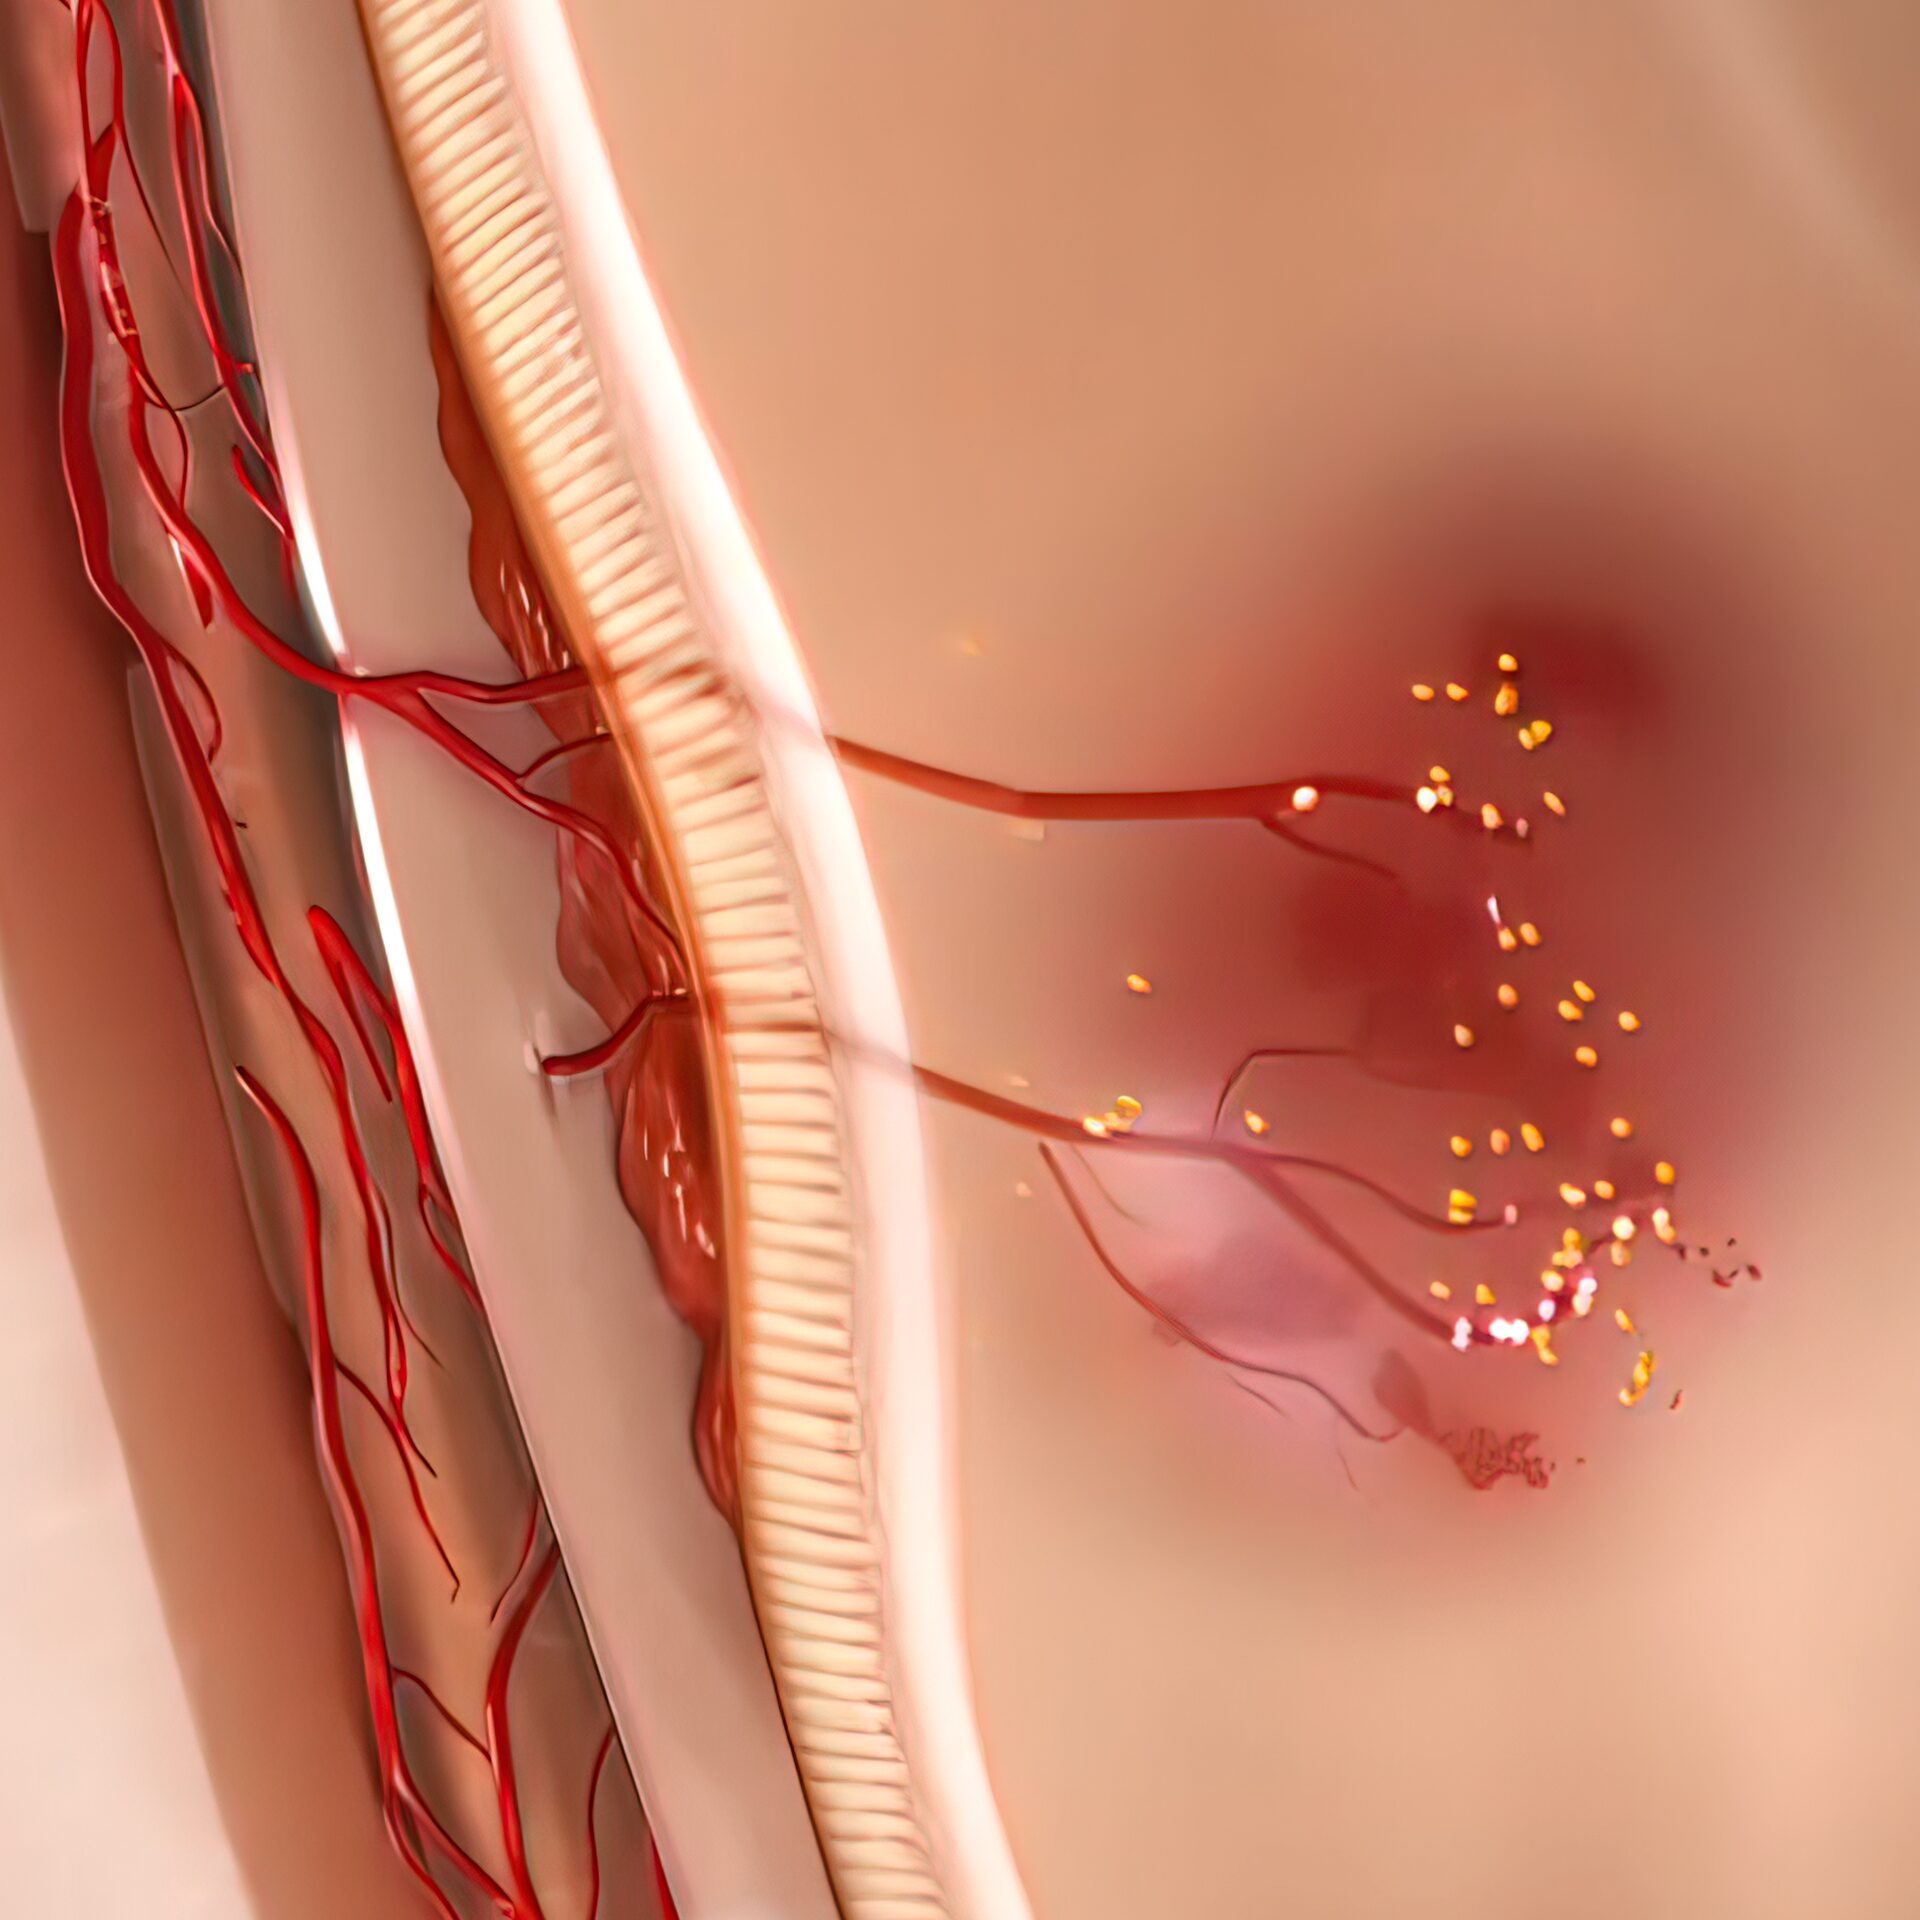

염증 완화 및 붓기 감소

산소는 염증 반응을 억제하고 조직의 회복을 빠르게 하여 레이저 시술 후 발생할 수 있는 붓기나 염증 반응을 줄이는 데 효과적입니다.

산소는 염증 반응을 억제하고 조직의 회복을 빠르게 하여 레이저 시술 후 발생할 수 있는 붓기나 염증 반응을 줄이는 데 효과적입니다.

새로운 혈관도 생성이 되나요?

기압을 높이면 적혈구와 결합하지 않아도 산소 분자 그대로 혈액 속으로 녹아들어 모세혈관과 세포까지 활성화되어 새로운 혈관들이 생성될 수 있는 환경을 조성합니다